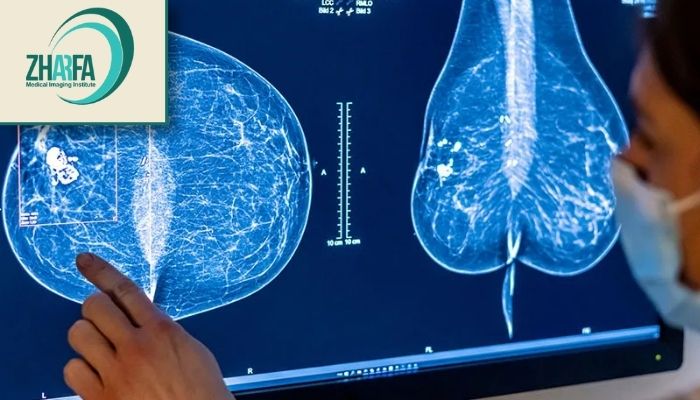

در مرکز ژرفا از تکنولوژیهای نوین و پیشرفته مانند رادیوگرافی دیجیتال و سونوگرافی استفاده میشود که امکان تشخیص دقیق و زودهنگام بیماریها را فراهم میآورد. این تجهیزات پیشرفته بهویژه برای شناسایی بیماریها در مراحل اولیه و تودههای کوچک بسیار مؤثر هستند و به پزشکان کمک میکنند تا تصاویر واضح و دقیق از ساختارهای داخلی بدن دریافت کنند.

دیجیتال: تصاویر در این روش مستقیماً روی رایانه ذخیره میشوند و امکان بزرگنمایی و بررسی دقیقتر توسط رادیولوژیست را فراهم میکنند.

سهبعدی یا توموسنتز: در این روش نوین تصاویر لایهبهلایه از بافت سینه گرفته میشود که به تشخیص بهتر تودهها و کاهش موارد مثبت کاذب کمک میکند.